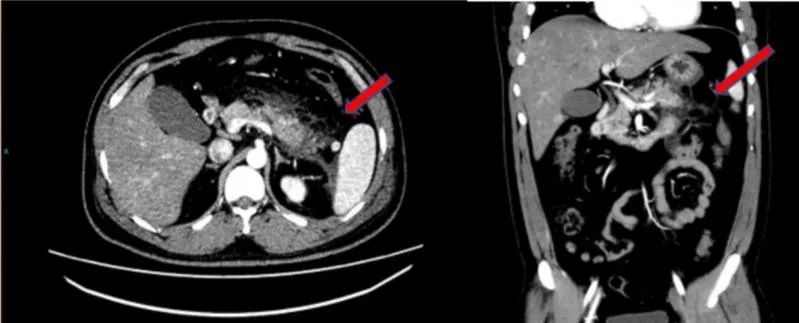

腹部增强CT提示胰腺尾部肿胀,胰腺周围脂肪间隙模糊,多发斑片状、条索影。红色箭头示胰腺脂肪间隙。

如图中箭头示意,小于血液置换过程中刚抽出的血为粉红色。